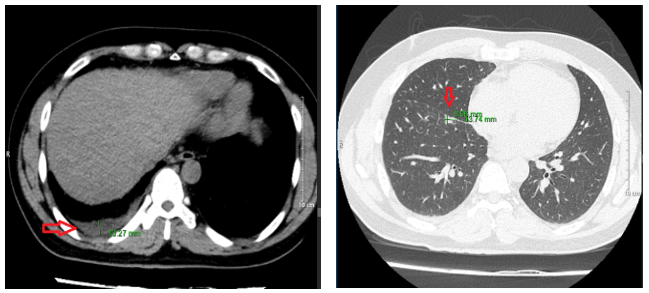

-        Chụp cắt lớp vi tính lồng ngực sau điều trị 10 tháng:  Nhu mô thùy trên sát rãnh liên thùy lớn có tổn thương dạng hang chứa khí kích thước 18x13mm, thành dày, có xơ hóa lân cận. Nhu mô phổi còn lại có vài nốt đặc, nốt lớn nhất đường kính 6mm. Phổi trái có vài nốt đặc bờ đều đường kính 5 mm.

Hình 4: Hình ảnh chụp cắt lớp vi tính lồng ngực sau điều trị 10 tháng: các nốt tổn thương gần hết và không có tràn dịch màng phổi

-        Chụp cắt lớp vi tính ổ bụngNốt đặc xương thân -cánh trái xương cùng kích thước 15x8mm và xương cánh chậu trái kích thước 13x9mm. Hình ảnh theo dõi u máu gan phải/ gan nhiễm mỡ

Hình 5: hình ảnh chụp cắt lớp vi tính ổ bụng sau điều trị 10 tháng không có tổn thương nghi ngờ thứ phát